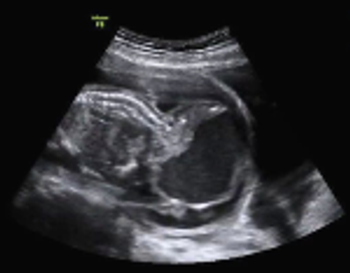

After a discrepancy between gestational age and fundal height, an ultrasound exam revealed one of the most common congenital tumors deriving from germ cells.